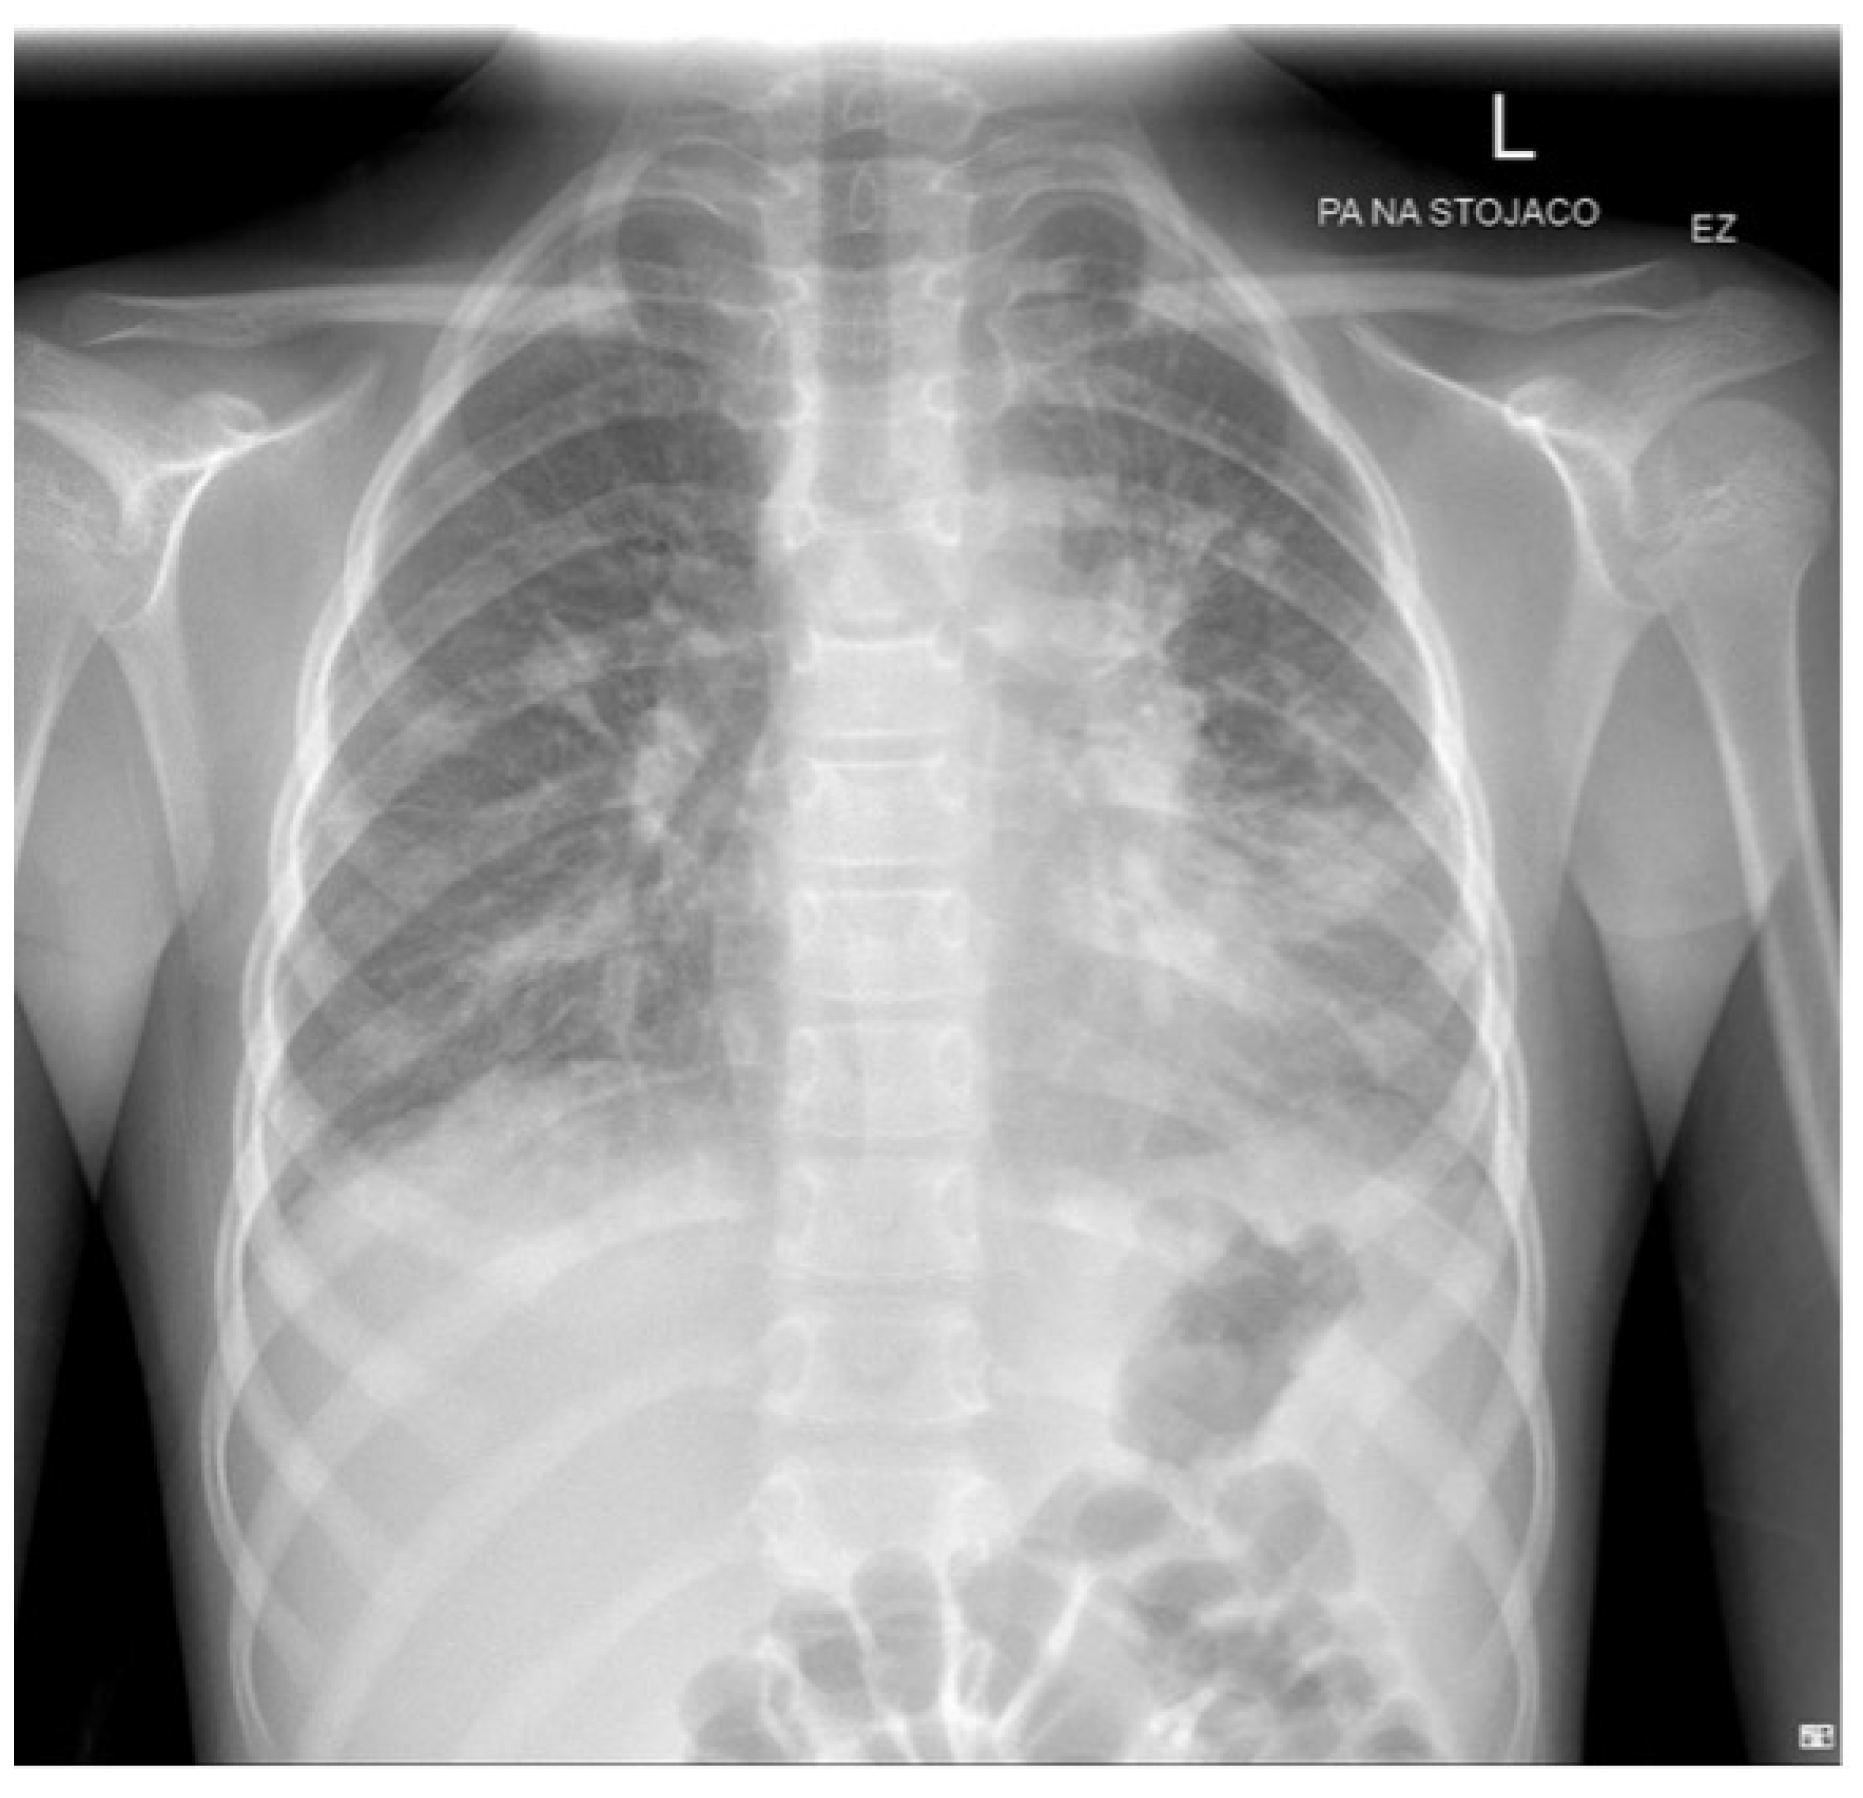

| Clinical and laboratory evidence of atypical pneumonia | Clinical: fever, cough, auscultatory changes. |

| Laboratory: increase in IgM MP antibodies, MP in oropharyngeal or follicular cultures, PCR. |